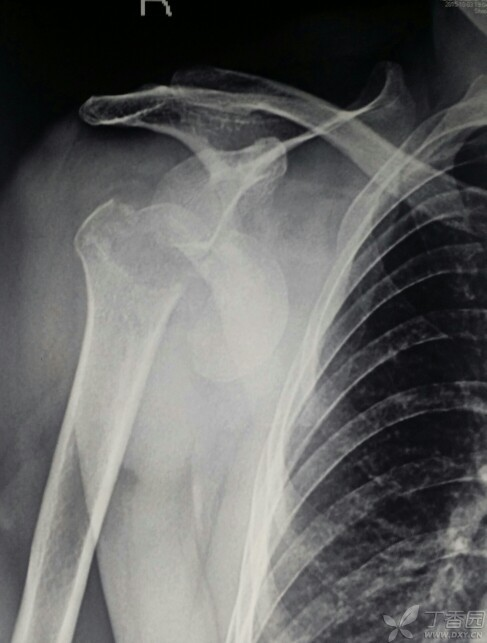

锁骨骨折大家一定都觉得很简单,但锁骨骨折也有一个并不少见的坑,看看下面的病例:

这个锁骨骨折简单吗?简单!做不就完了吗?

做完了,骨折解剖复位漂亮吧?干得漂亮!等等!怎么肩锁关节脱位了 ……

这个锁骨骨折简单吗?另一位网友分享:

等下,拍个双侧对比看看,锁骨骨折合并肩锁关节脱位,还好术前发现了 ……

这样的病例少吗?还真不少,一搜一大把!

6.8% 的锁骨中段骨折患者伴有同侧肩锁关节脱位。这个坑也不能踩啊!